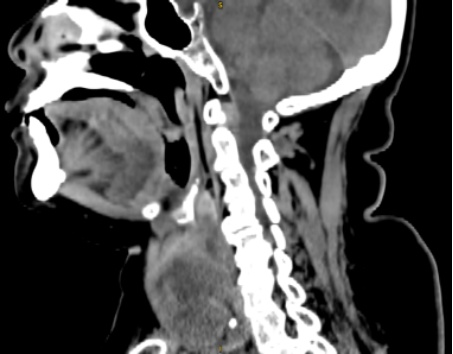

患者女,84岁,主诉发现胸骨后甲状腺肿合并呼吸困难4天于2022年8月31日入院。神清合作,自主体位,肥胖体型,呼吸困难,急性病容,颈软,气管居中,未见皮疹、瘢痕,颈前局部无明显隆起,未扪及包块、表面无血管杂音。无颈静脉充盈。颈部淋巴结未扪及明显肿大。甲状腺左、右侧叶及峡部未扪及明显包块。入院后实验室检查:游离三碘甲状腺原氨酸(FT3) 3.25 pmol/L (参考值2.43~6.01 pmol/L),游离甲状腺素(FT4) 6.92 pmol/L (9.01~19.05 pmol/L),促甲状腺激素(TSH) 54.43 uIU/L (0.35~4.94 mU/L),抗甲状腺过氧化物酶抗体(Anti-TPO) 72.69 IU/L (<5.61 U/L),抗甲状腺球蛋白抗体(Anti-Tg) > 1000.00 U/L (<4.11 U/L)。床旁甲状腺彩超:甲状腺右侧叶大小约19 × 19 × 43 mm,峡部厚约6.2 mm,左侧叶大小约35 × 40 × 53 mm,甲状腺形态欠规则,双侧不对称,实质光点增粗,回声增强,分布不均。CDFI:上述低回声结节内部可见少许血流信号。甲状腺肿大并实质弥漫性病变:双侧颈部多发实性结节,考虑淋巴结。甲状腺CT平扫 + 增强:支气管疾患并肺部感染、胸骨后甲状腺肿、冠状动脉粥样硬化(见图1(a)~(c))。既往史:既往高血压病,最高血压160/95 mmHg,口服苯磺酸左氨氯地平片,控制可,有“睡眠呼吸暂停综合征”,未予治疗。

(a) (b) (c)

(a) 甲状腺CT水平面;(b) 甲状腺CT矢状面;(c) 甲状腺冠状面。

Figure 1. Thyroid CT scan

1. 甲状腺CT检查